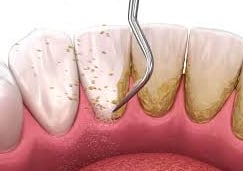

Deep Cleaning, also called Scaling and Root Planing (SRP), is a non-surgical treatment for gum disease. During this procedure, the hygienist cleans deep under the gums and smooths the roots of your teeth. This reduces inflammation, stops infection from getting worse, and helps gums heal and reattach to the teeth.

Deep cleaning, also known as scaling and root planing, is used to treat gum disease by removing plaque and bacteria from below the gum line and smoothing the tooth roots to help gums heal properly. Depending on the severity of the condition, the treatment may be completed in sections (such as half-mouth or quadrant visits) to ensure comfort and thorough care. After deep cleaning, ongoing periodontal maintenance visits every 3–4 months are essential to keep gum disease under control, as regular cleanings are not sufficient once periodontal issues are present.

Scaling — removing buildup from below the gumline

Root planing — smoothing the roots to help gums heal